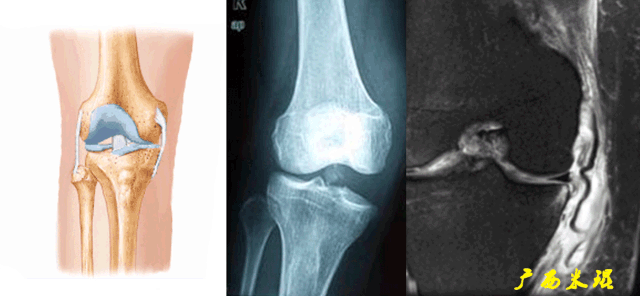

5)Segond骨折:

胫骨平台前外侧撕脱骨折(胫骨平台腓骨尖上方,关节线下方的撕脱骨折),多因为下肢过度内翻加内旋暴力所致。

-

骨折本身无特殊治疗,但其强烈提示ACL损伤(75–100%)。

6)胫骨前移:

胫骨后缘垂直线位于股骨髁后缘垂直线前方5mm以上。